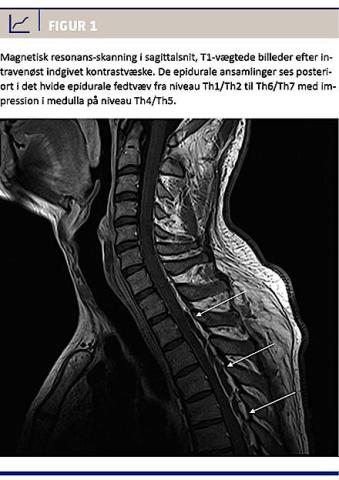

I løbet af det første indlæggelsesdøgn fik han urinretention. En akut MR-skanning viste epidurale ansamlinger posteriort fra Th1 til Th7 med impression i medulla på niveau Th4/Th5 (Figur 1). Fundet var foreneligt med spinale epidurale abscesser. I samråd med neurokirurgisk og mikrobiologisk afdeling fortsattes den antibiotiske behandling.